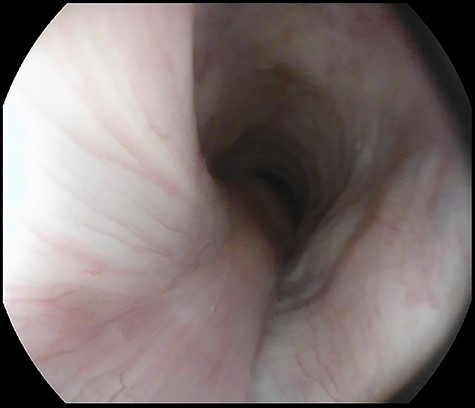

A 77-year-old man was referred for a long history of heartburn and more recent onset of progressive regurgitation, dysphagia and weight loss. Empirical therapy with proton-pump inhibitors was ineffective. The gastroesophageal reflux disease health-related quality of life (GERD-HRQL) score was 22. The functional outcome swallowing scale (FOSS) score for dysphagia was 2. Physical examination was unremarkable. Upper gastrointestinal endoscopy showed a soft submucosal bulging in the posterior wall of the distal esophagus located between 29 and 39 cm from the incisors, and 3 cm proximal to the esophago-gastric junction (Fig. 1). Computed tomography of chest and abdomen showed a fat-density submucosal mass with luminal narrowing (Fig. 2). High resolution manometry (HRM) showed pan-esophageal pressurization in 100% of the swallows and a resting lower esophageal sphincter (LES) pressure of 11.2 mmHg (Fig. 3). Through a laparoscopic transhiatal approach, esophageal myotomy, mass enucleation, suture approximation of the muscle layer, posterior cruroplasty, and 270° Toupet fundoplication was performed (Fig. 4). The procedure took 55 min. Postoperative course was uneventful. A gastrographin swallow study on Day 1 showed a normal esophagogastric transit and the absence of leaks. The patient was discharged home on postoperative Day 2. Pathology confirmed the clinical suspicion of esophageal lipoma (Fig. 5). High-resolution manometry was repeated at the 6 month follow-up and showed an ineffective esophageal motility, with 50% of non-conducted swallows. The resting LES pressure increased (17.4 mmHg), and the swallow-induced LES relaxation was normal. The GERD-HRQL score was 3 and the FOSS score was 0.

Upper gastrointestinal endoscopy showing submucosal lipoma of the distal esophagus extending between 29 and 39 cm from the incisors.